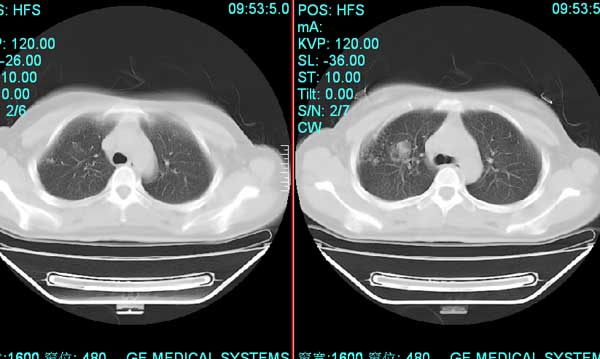

以下是引用pujunzhi在2008-7-1 20:03:00的发言:[br]支持楼主意见!两肺继发性肺结核伴多发空洞形成。